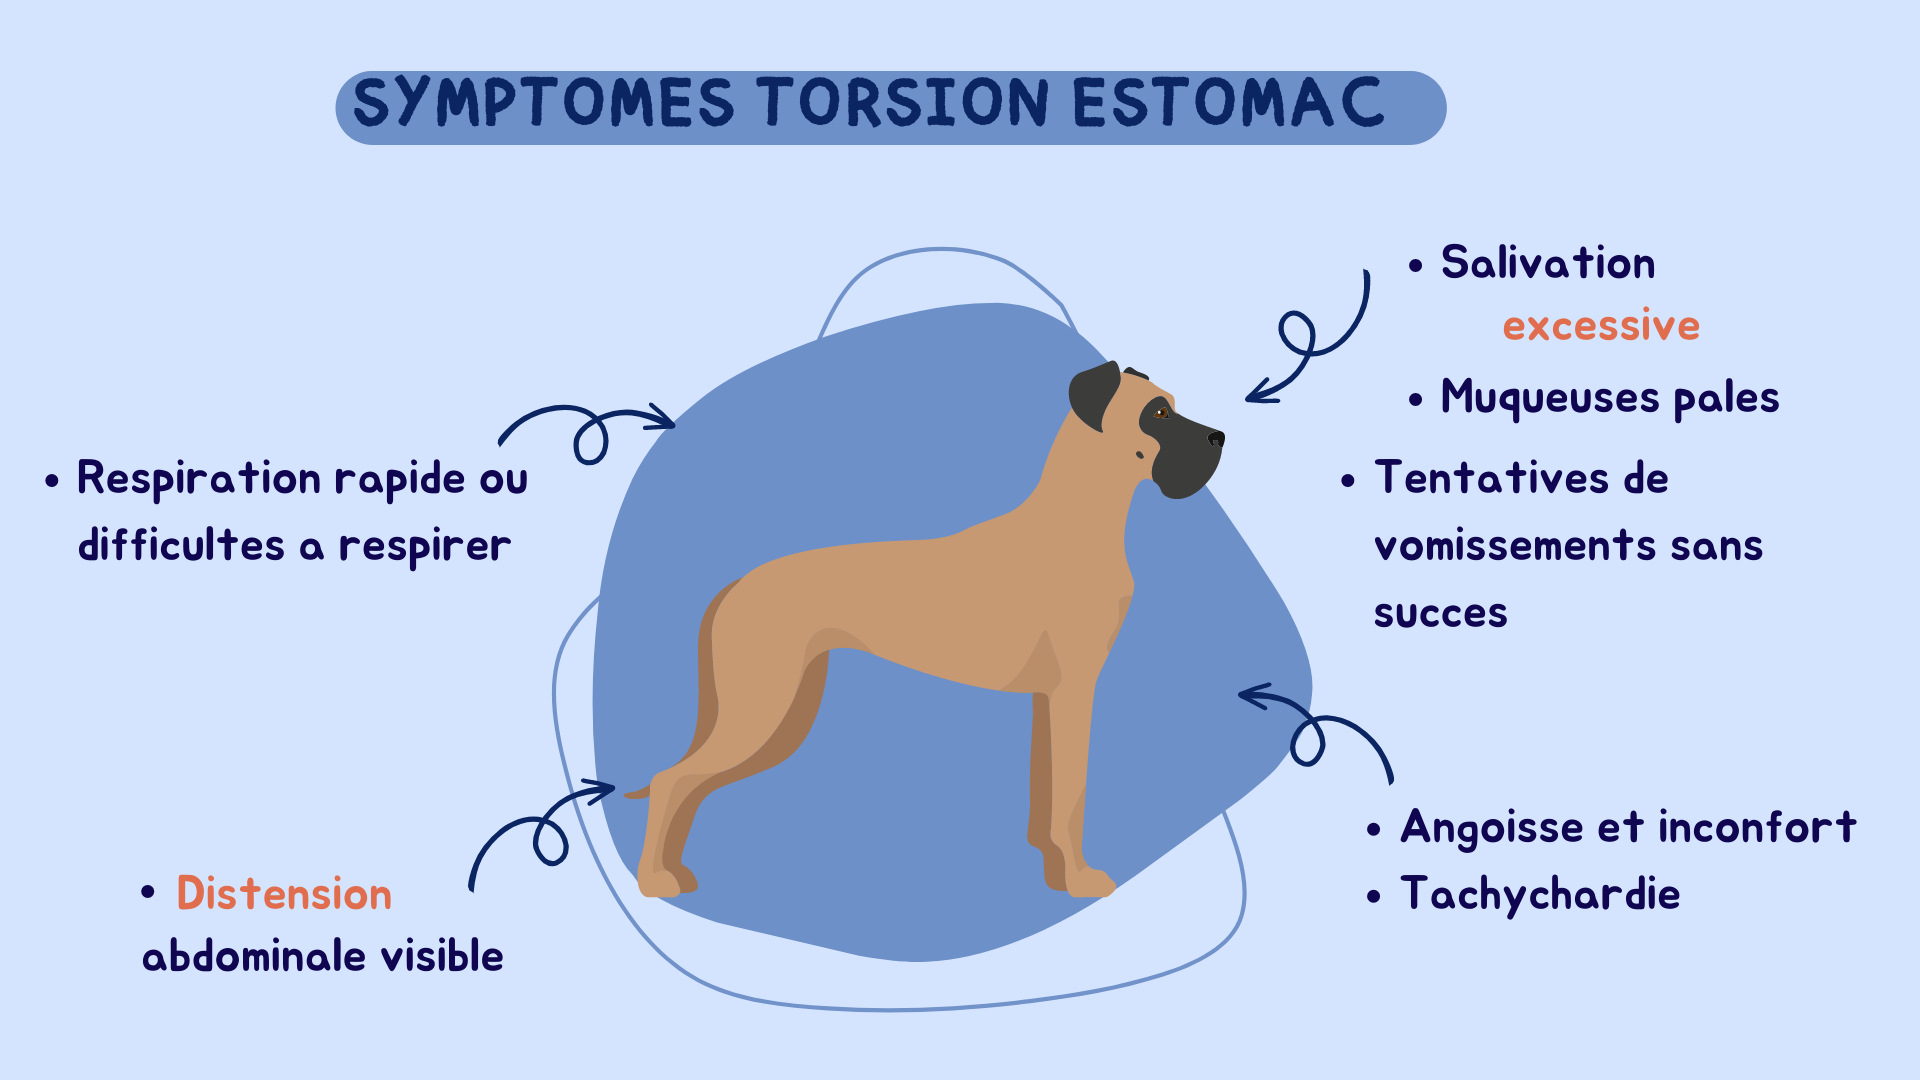

Symptome torsion estomac chien

Il est essentiel de reconnaître les signes de la torsion de l'estomac chez le chien, car une intervention rapide peut sauver la vie de l'animal.

Certains symptômes sont légers ou absents lors du stade précoce, cependant, si vous suspectez que votre chien puisse être en train de subir une dilatation de l'estomac, contactez votre vétérinaire immédiatement.

Les symptômes courants incluent:

- distension abdominale visible,

- tentatives de vomissements et haut-le-coeur sans succès,

- agitation liée à l'inconfort,

- salivation excessive,

- respiration rapide et difficultés à respirer,

- muqueuses pâles,

- abattement,

- comas,

- mort.

Un chien en SDTE montre principalement une agitation, des nausées et haut-le-coeur avec hypersalivation.

Il peut toutefois cracher de la salive puisque sa production ne peut être régulée du au blocage de l'estomac.

L'estomac peut apparaître distendu ou non en fonction du stade de l'atteinte.

Les chiens n'expriment pas la douleur de la même manière.

Certains vont être abbatus et léthargiques pendant que d'autres feront des vocalises.

La respiration est affecté et entraine une arythmie.Certains chiens s'écroulent et n'arrive plus à se relever.